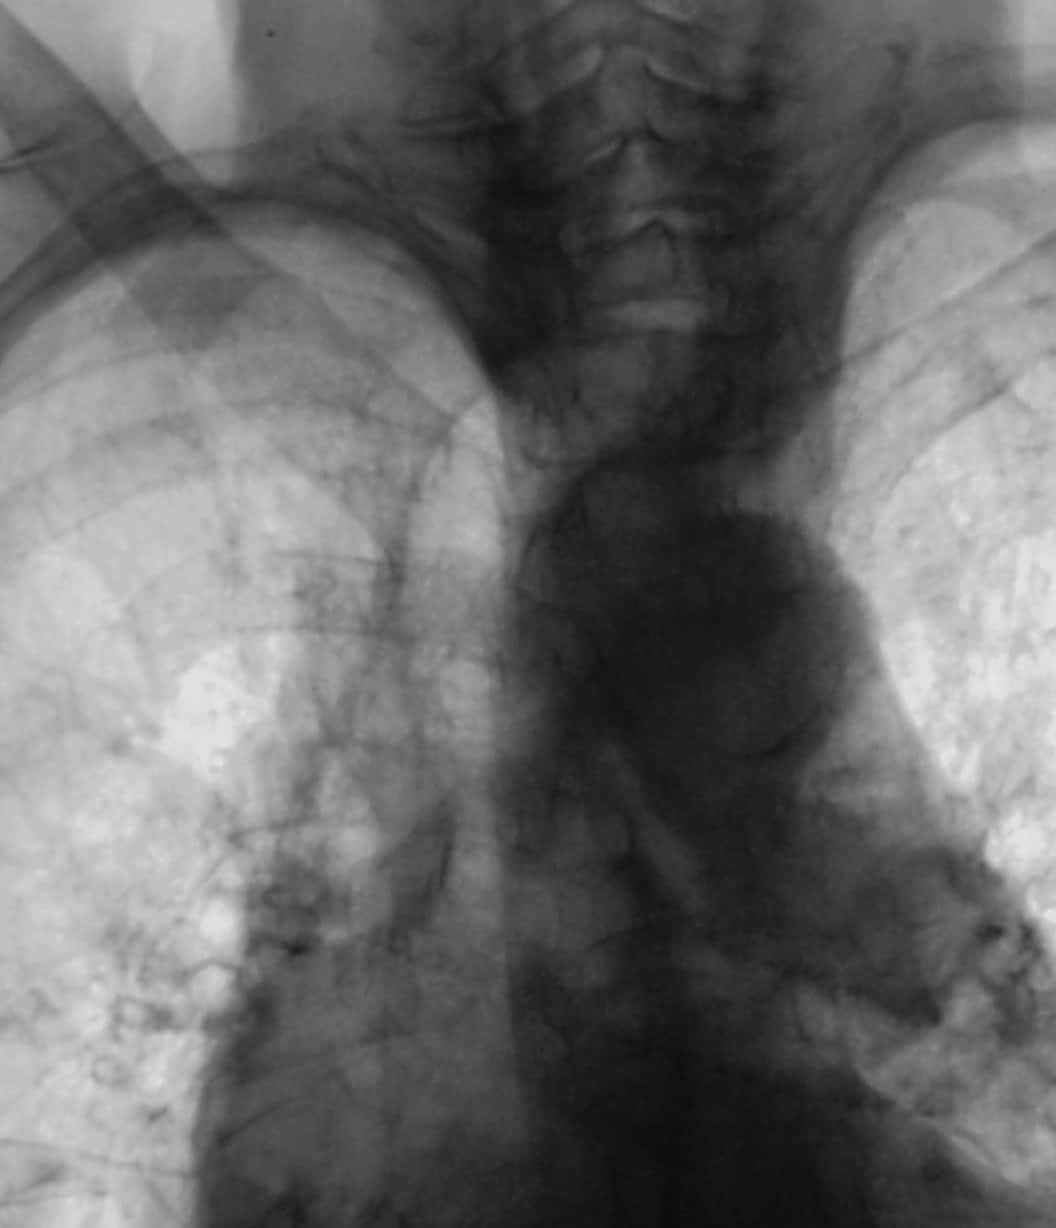

- Рентген грудной клетки (на фото). Проводится рентгенография в прямой и боковой проекциях. На рентгенограмме выявляется равномерное затемнение.

Правосторонняя среднедолевая пневмония на рентгенограмме

- рентгенография. При правосторонней среднедолевой пневмонии на рентгеновском снимке визуализируется затемнение участка в средней доле правого легкого, наличие одиночного или множественных очагов;